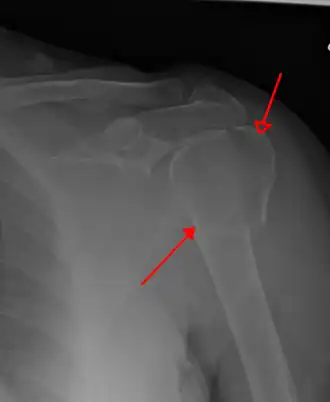

La fracture de l'extrémité supérieure de l'humérus est la rupture de la partie haute de l'os supérieur du bras, l'humérus, en deux ou plusieurs fragments.

Le diagnostic de cette fracture s'effectue par radiologie médicale, complété par un scanner et une reconstruction 3D à partir d'images en cas d'indication chirurgicale[2].